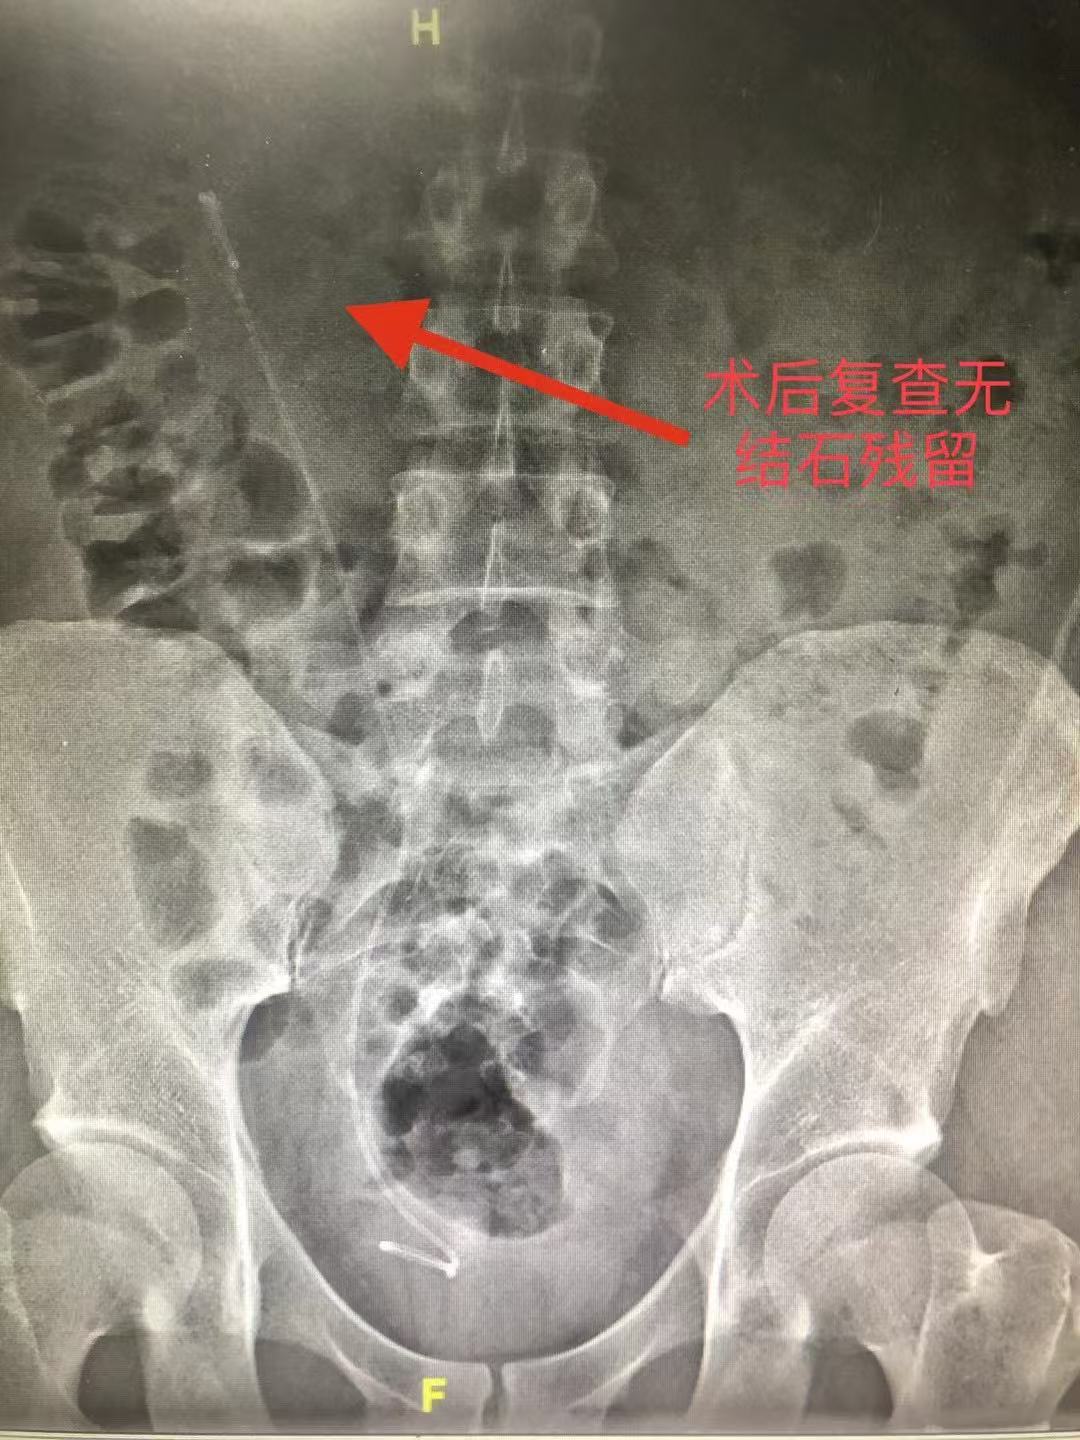

术后患者未出现发热、出血等并发症,术后第一天拔除导尿管并恢复自主排尿,复查腹部平片未见明显结石残留。术后第三天患者步行出院,出院时血肌酐值稳定,腰痛症状完全缓解。相较于传统开放手术或经皮肾镜手术,该术式显著缩短住院时间,减轻术后疼痛,实现“无创口、快恢复”的治疗目标。